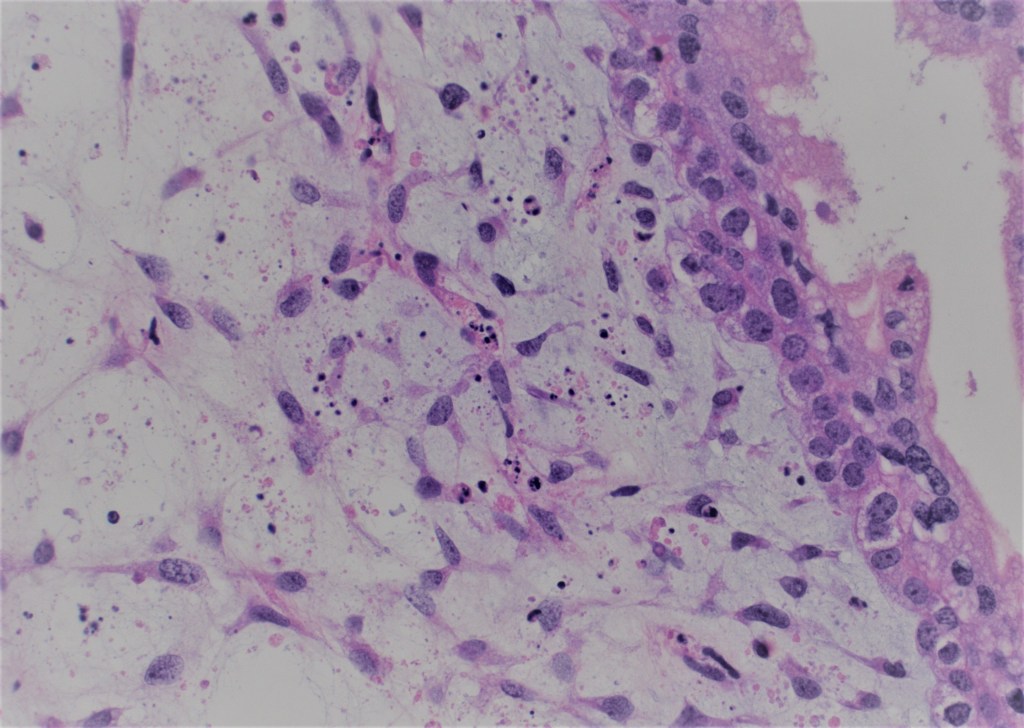

- Presence of cisterns, circumferential or almost circumferential trophoblastic proliferation and trophoblastic inclusions (figure 3-4).

- Blue myxoid stroma with karyorrhexis (figure 5).